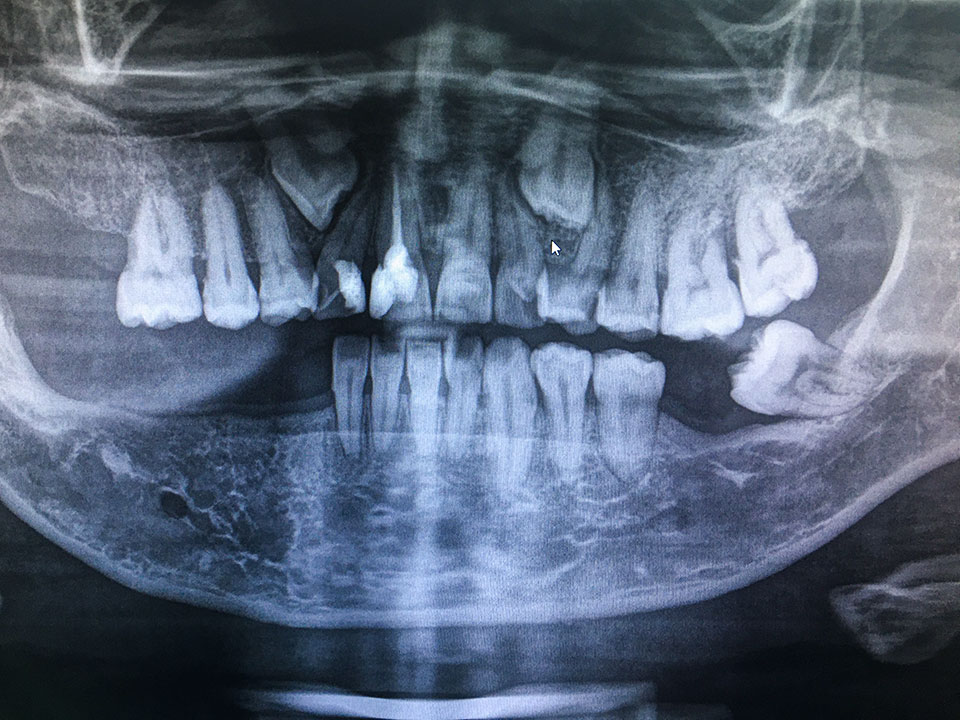

Panoramablick auf Ihre Zähne

Bei der Aufnahme fährt der Röntgenkopf einmal im Halbkreis um Ihren Kopf herum. Dabei nimmt sie schichtweise das gesamte Gebiss auf. Die Aufnahme zeigt alle Zähne im Ober- und Unterkiefer, den Kieferknochen sowie die beiden Kiefergelenke und die Kieferhöhlen rechts und links.

Die Panorama-Schichtaufnahme gibt einen guten Gesamtüberblick über den Kauapparat. Sie zeigt, ob es retinierte Zähne gibt, d.h. solche, die noch nicht oder nicht ganz durchgebrochen sind, oder verlagerte Zähne, die am falschen Platz stehen oder in die falsche Richtung wachsen. Solche Probleme kommen häufig bei Weisheitszähnen vor. Weicht ein Zahn von seiner normalen Achse ab und schiebt sich dabei gegen einen Nachbarzahn, kann das dessen Wurzel beschädigen. Auszumachen sind auch Veränderungen des Kieferknochens, der Kieferhöhlenschleimhaut, an Nerven oder Gefäßen.

So können wir potenzielle Probleme frühzeitig erkennen und gefährdeten Zähnen mit kieferorthopädischen oder chirurgischen Maßnahmen helfen. Vor dem Setzen von Zahnimplantaten bestimmen wir die optimale Position für die neuen künstlichen Zahnwurzeln.